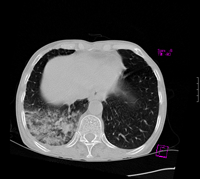

标题: CT9563:女67岁,咳嗽咯白痰伴纳差一月。右肺呼吸音低可闻及 [打印本页]

女67岁,咳嗽咯白痰伴纳差一月。右肺呼吸音低可闻及湿罗音。白细胞及淋巴细胞不高,无发烧

1、右上胸廓塌陷,纵隔气管右移

2、病灶靠后方,一般结核多见一点

3、病灶内,纵隔内有少许钙化灶

3楼的肺细支气管肺泡癌也不能完全排除,毕竟患者年纪大,病史短,临床上感染症状不明显,建议短期内复查吧

病灶范围较大,病史较短,病人年龄较大,结核中毒症状不明显, 考虑1右肺细支气管肺泡癌,2.硬化性淋巴瘤,建议进一步检查